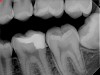

Figure 19. Preoperative radiograph of a case demonstrating apical periodontitis. Courtesy of Dr. Allen Ali Nasseh.

Figure 19

This sealer solves most, if not all, of the previous problems of traditional sealers. Therefore, a thicker layer of sealer can be used because it is dimensionally stable and does not wash out. The core is used only as a hydraulic pump to move the sealer into place and allow for post space preparation or a pathway for retreatment. In addition and most importantly, the root canal preparation can be conservative and better adapted to restorative needs, since a traditional gutta-percha point (and not a metal plugger) is used to move the filling material. An additional benefit of the system is that there are now gutta-percha points that are impregnated with nano particles of bioceramics, so the sealer bonds not only to the root surface but also to the outer surface of the gutta-percha, eliminating the gap between the two (Figure 19 through Figure 21).